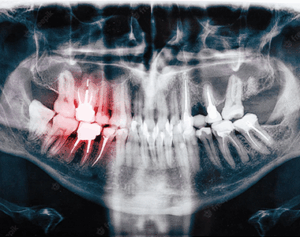

Why would I need an x-ray? Early tooth decay does not tend to show many…